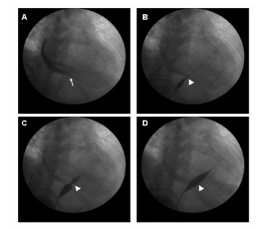

Hình 1: Quá trình nong bóng màng ngoài tim dưới màn tăng sáng

- Xác định vị trí bóng nong bằng cách bơm nhẹ bóng, đảm bảo eo bóng nằm đúng vị trí lá thành màng ngoài tim (đối với bóng Inoue), bóng nằm giữa màng tim với bóng ngoại biên

- Sau đó bơm bóng nở tối đa (khoảng 3cm). Bơm bóng tối đa là khi phần eo của bóng mất đi.

- Bơm bóng thêm 2-3 lần nữa để đạt hiệu quả tối ưu.